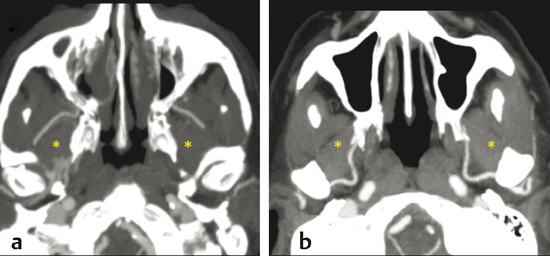

It gives off two main branches, the posterior lateral nasal artery (PLNA) and the posterior septal artery (PSA), 1 , 2 which can be divided into one or two trunks medial to the ethmoidal crest, before or after crossing the sphenopalatine foramen. It is rarely possible to identify more than two trunks. 1 , 3 The PLNA supplies the region of the lateral nasal wall giving off branches to the inferior turbinate (inferior turbinate artery), middle turbinate (middle turbinate artery), mucosa of the fontanelle, and to the mucosa of the maxillary sinus 4 (Fig. 3‑3, Fig. 3‑4). In approximately 20% of cases this artery supplies the superior turbinate. 5 The inferior turbinate artery enters a bony canal and runs anteriorly along the turbinate. It usually gives off two terminal branches, within or adjacent to the bone, supplying the mucosa of the turbinate (Fig. 3‑5). The artery gives off several small vessels to the maxillary sinus and to the ethmoidal complex. The middle turbinate artery gives off several branches, some of which run along the medial surface of the turbinate whereas the other branches supply the lateral turbinate surface and anterior ethmoidal complex (see Fig. 3‑3).